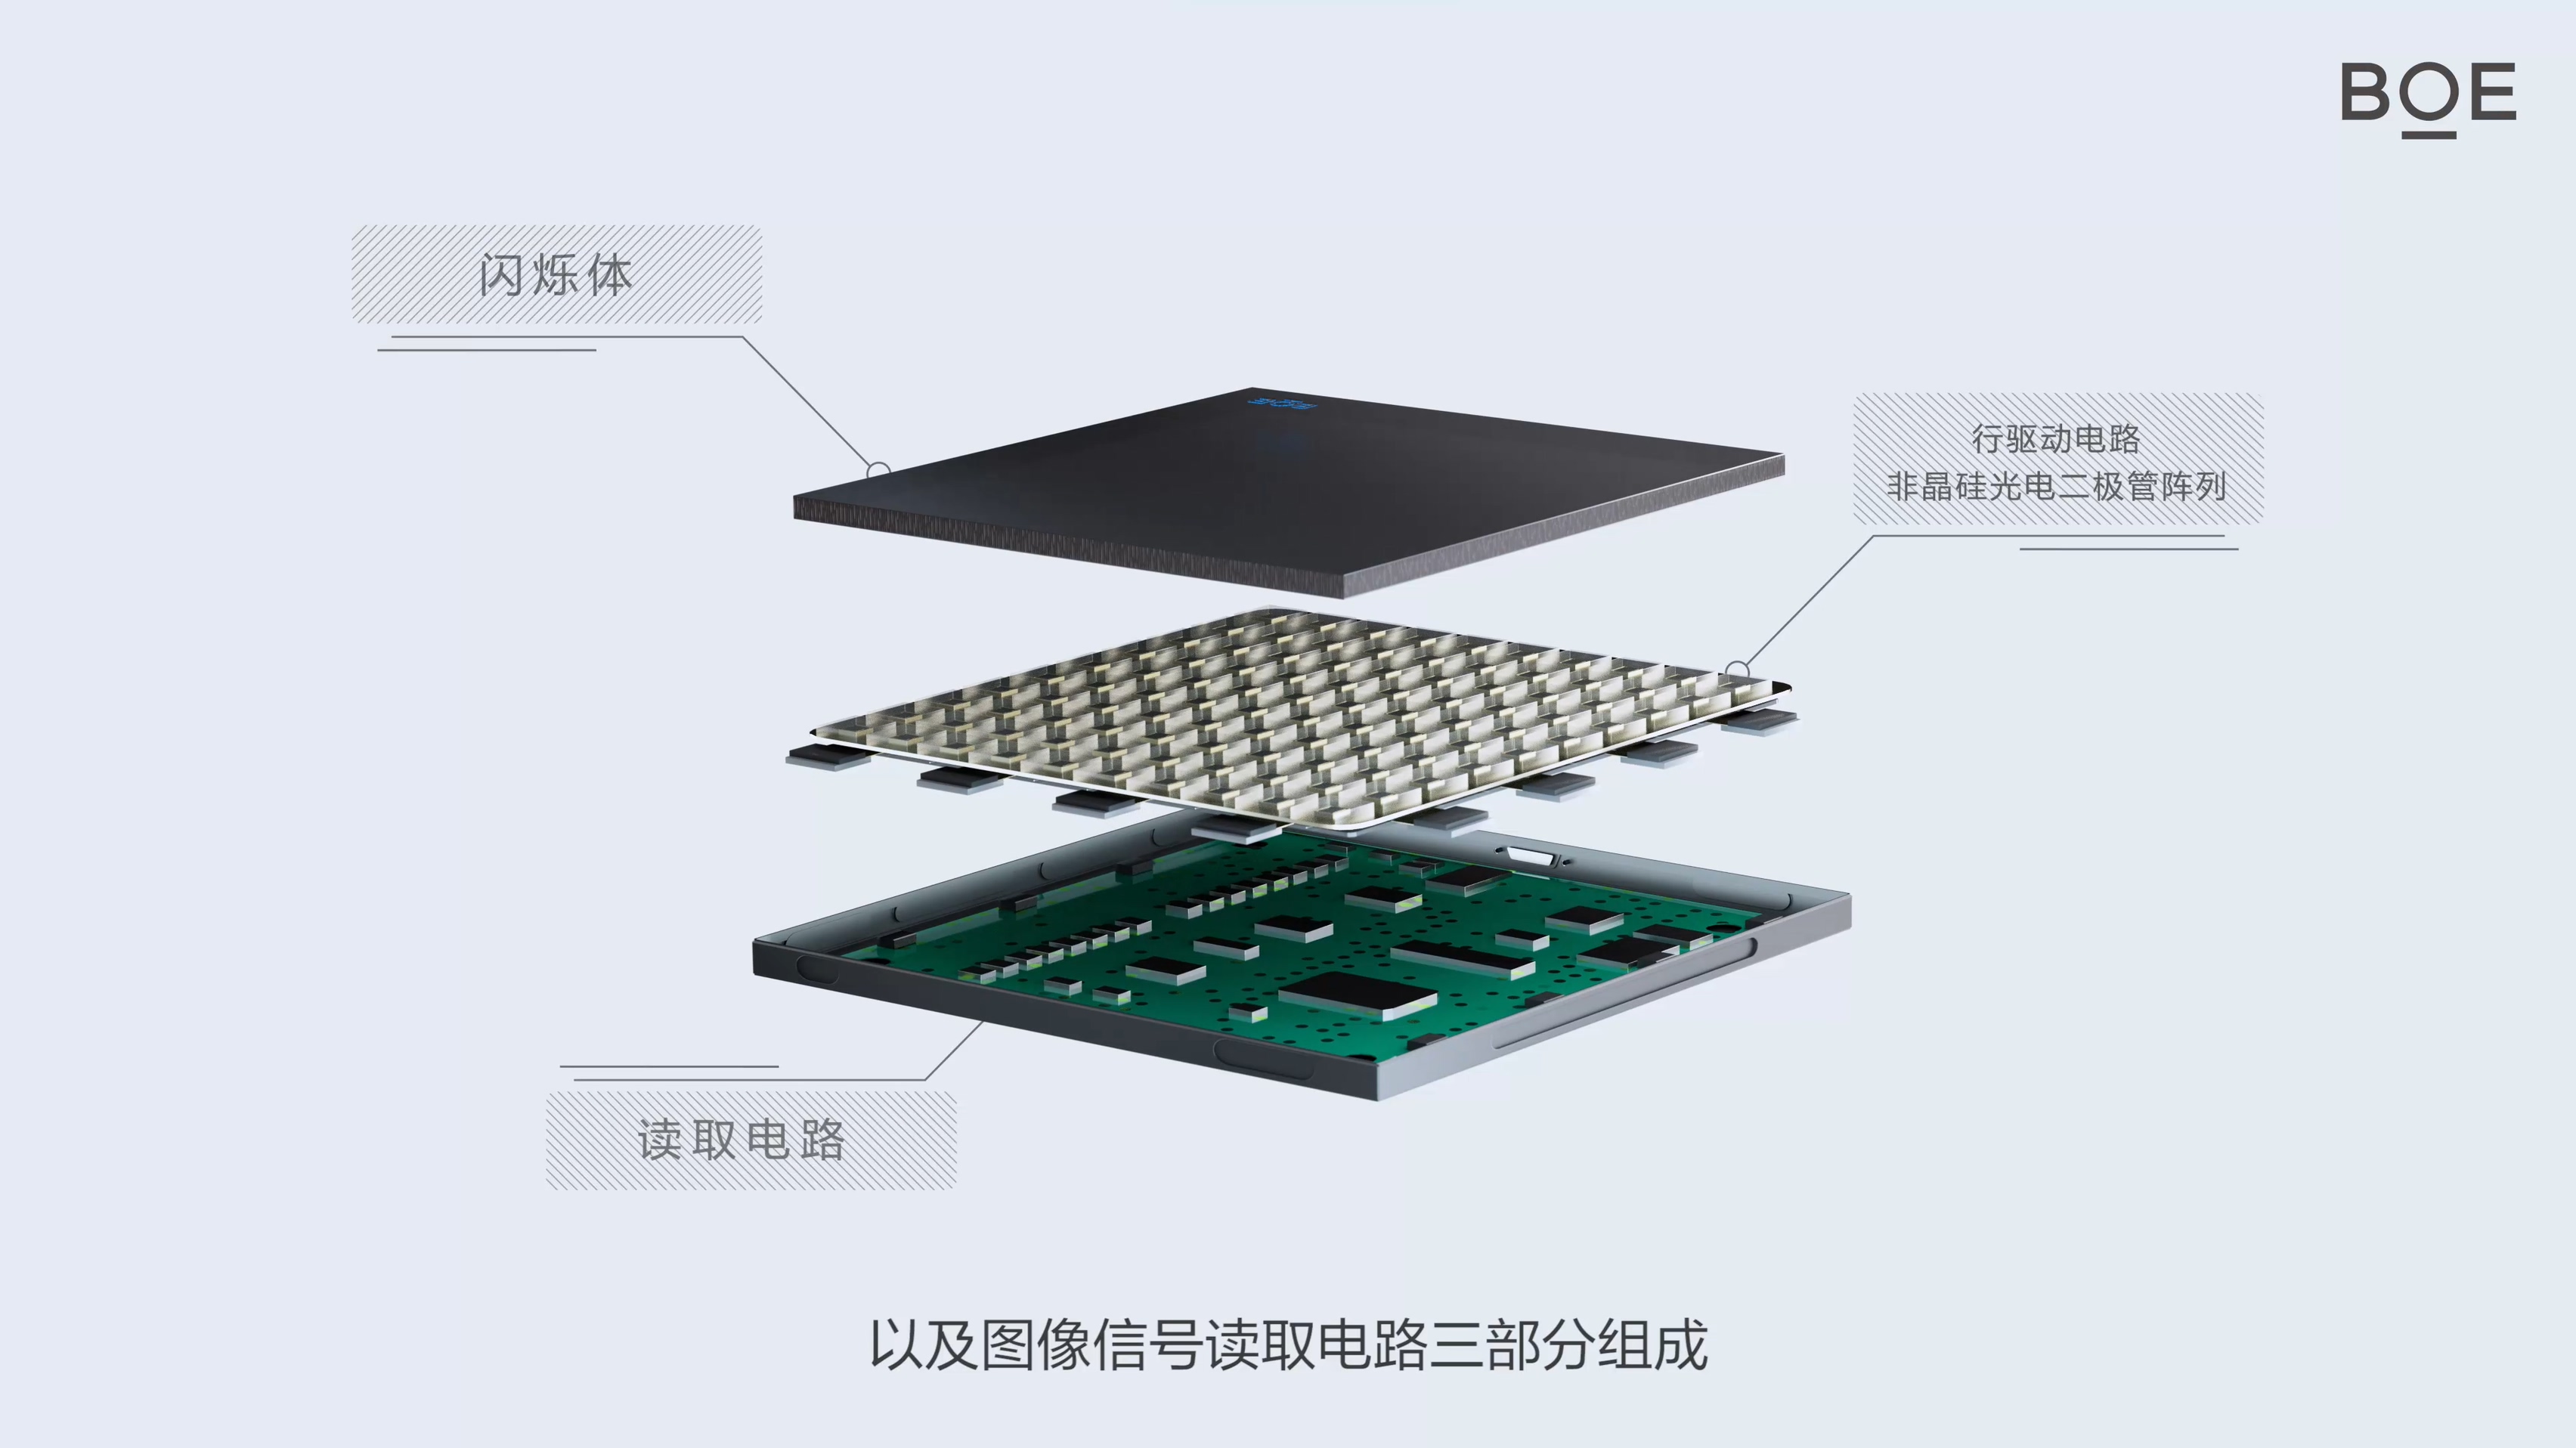

Medical Imaging

The X-ray detector backplane independently developed by BOE features low dose, high resolution, high conversion efficiency, high signal-to-noise ratio, and wide dynamic range, which can be widely used in medical and industrial fields.